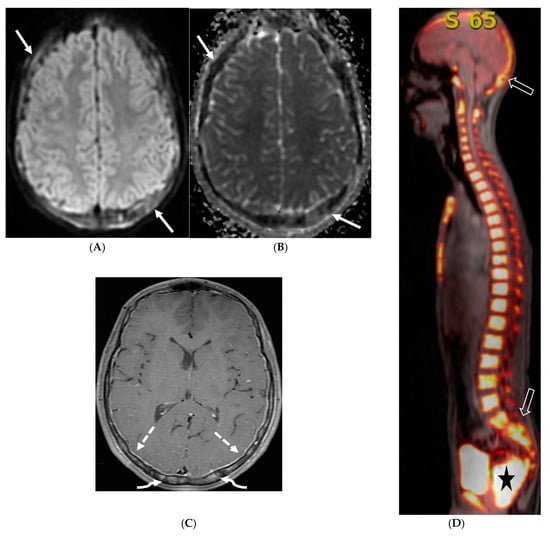

4.4. Systemic Meningeal Metastases (SMM)

Meningeal metastases from an extracranial primary tumor is a diagnosis with a grave prognosis, reducing the survival to less than 3 months if left untreated. Early and accurate diagnosis is essential for improving patient outcomes [84]. Leukemias and neuroblastoma are the most common primary malignancies in the pediatric population [85,86]. Leukemia is the only one which merits prophylactic treatment to avoid SMM.

The typical MRI presentation of SMM involves serpentine, nodular, or plaque-like enhancement in sulcal spaces, basal cisterns and along the cauda equina nerve roots [87,88]. Notably, SMM enhancement on post contrast [PC]-T1 images is superior to the PC-FLAIR in contrast to that seen in infectious meningitis [84]. However, in case of a non-enhancing primary tumor, FLAIR and DWI are important sequences to look for SMM. Hydrocephalus and subependymal deposits are other common features found in kids with SMM (Figure 15, Figure 16 and Figure 17). Positive cytology on CSF analysis, especially with leukemia, is important [89].

Figure 15.

Axial DWI (A), axial ADC (B), axial T1 FS post contrast (C) and Fluorodeoxyglucose Positron Emission Tomography (FDG–PET) scan (D): 13-year-old male with bilateral leg pains, headache, fever and weight loss: Blood tests and CT scan were concerning for Burkitt’s lymphoma. There is heterogeneous calvarial bone marrow signal with restricted diffusion (arrows) and patchy enhancement (curved arrows). Diffuse thickening and enhancement of pachymeninges in the supratentorial compartment is noted (dashed arrows). Findings are most consistent with lymphomatous involvement. Multifocal diffuse/heterogeneous pattern of FDG uptake within the axial and appendicular skeleton and the calvarium (open arrows). Intense FDG avid uptake is seen in the presacral mass (star).

Figure 16.

16-year-old female with 4 months history of globus sensation and recent botox injection of lower esophageal junction. Headache and vomiting for past week: Esophagogram (A), Axial T2 orbits (B), axial FLAIR (C) and post contrast T1 (D,E): Narrowing of the Gastroesophageal (GE) junction with beaked configuration and mild distention of the lower esophagus likely from early achalasia (black arrow). There is bilateral papilledema indicating raised ICP (dashed arrows) and sulcal hyperintensity (curved black arrows). Diffuse LME in the supra-and-infratentorial regions and along optic sheaths raising the concern for leptomeningeal carcinomatosis (white arrows). Pathology: Gastric adenocarcinoma metastasis.

Figure 17.

Axial T2 FS (A), axial Susceptibility weighted imaging (SWI) (B), axial DWI (C), post contrast sagittal and axial T1 post contrast (D,E): 19-year-old female with history of stage IV neuroblastoma, left paraspinal primary ganglioneuroblastoma, treated with chemotherapy, radiation and bone marrow transplant presents with headache. There are extensive hemorrhagic leptomeningeal masses, both supra and infratentorial region (arrows). The lesions also demonstrate restricted diffusion which could be secondary to internal hemorrhage or high cellularity of the tumor(curved arrows). The larger masses invade the cortex of both cerebral hemispheres, with surrounding vasogenic edema (black arrow). Avid enhancement of the lesions is seen along with overlying dura (dashed arrows). Features are in keeping with extensive leptomeningeal metastatic neuroblastoma.